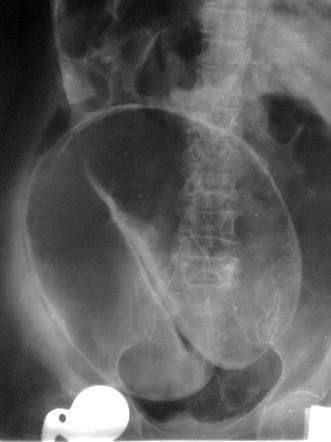

Coffee-bean sign on abdominal radiograph is indicative of large bowel obstruction, primarily due to sigmoid volvulus. The coffee-bean sign appears due to apposition of distended large bowel. Reference: https://radiopaedia.org/articles/coffee-bean-sign-sigmoid-colon Image via: https://radiopaedia.org/articles/coffee-bean-sign-sigmoid-colon